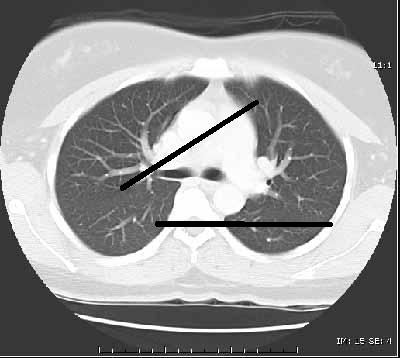

下面是一些样本图像。最左边的是它应该是什么样子,中间的那个是当它发现有一些黑线(不完全是黑色,但高于灰度强度的某个阈值),而在极右的那条是我期望的代码输出。

这是在CT扫描中发现裂缝时特别感兴趣的,在其他灰度背景中,裂缝以暗黑斑点/线条的形式出现。

例如,对于ct图像,我在示例图像中应用了您的“裂缝”,阈值这些裂缝会很好地工作(您只得到一些背景噪声/伪影)。请参阅下面的OpenCV片段:

cv2.imwrite('output.png',thresh)输入:

原始图像来源: www.radiologyinfo.org

输出: